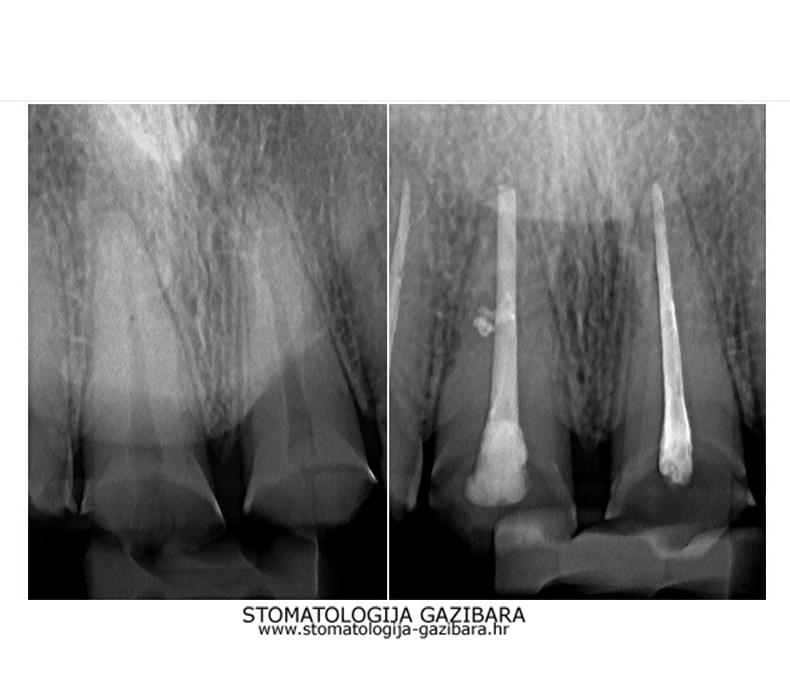

Endodoncija - liječenje korijena zuba

LIJEVO: 1a početno stanje,prednji zubi - DESNO: 1b nakon završetka terapijee LIJEVO: 2a revizija punjenja korijenskih kanala,višekorijenski zubi        <br />

DESNO: 2b nakon završetka terapije LIJEVO: 3a  prije revizije punjenja,jednokorijenski zub<br />

DESNO: 3b  nakon završetka terapije LIJEVO: 4a liječenje granuloma ,početno stanje<br />

SREDINA: 4b stanje nakon 9 mjeseci<br />

DESNO: 4c stanje nakon 3 godine, granuloma više nema !